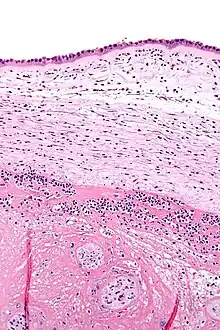

Histopathologie de la chorioamnionite. L'amnios (partie haute de l'image) présente des neutrophiles épars, ce qui permet de diagnostiquer une chorioamnionite.